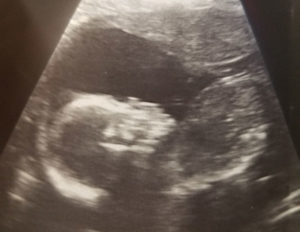

Here is my 20 weeks anatomy scan and everything is good.

Six years of trying after tubal reversal, with 7 IUI’s, 2 IVF’s, fertility accupuncture and 2 miscarriages and finally got pregnant on my own!